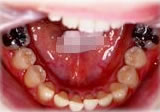

反対咬合(受け口)症例

初診時年齢24歳6ヶ月。前歯部反対咬合を主訴に来院。

骨格性反対咬合と診断し、外科的処置を併用して治療。

下顎 下顎 下顎